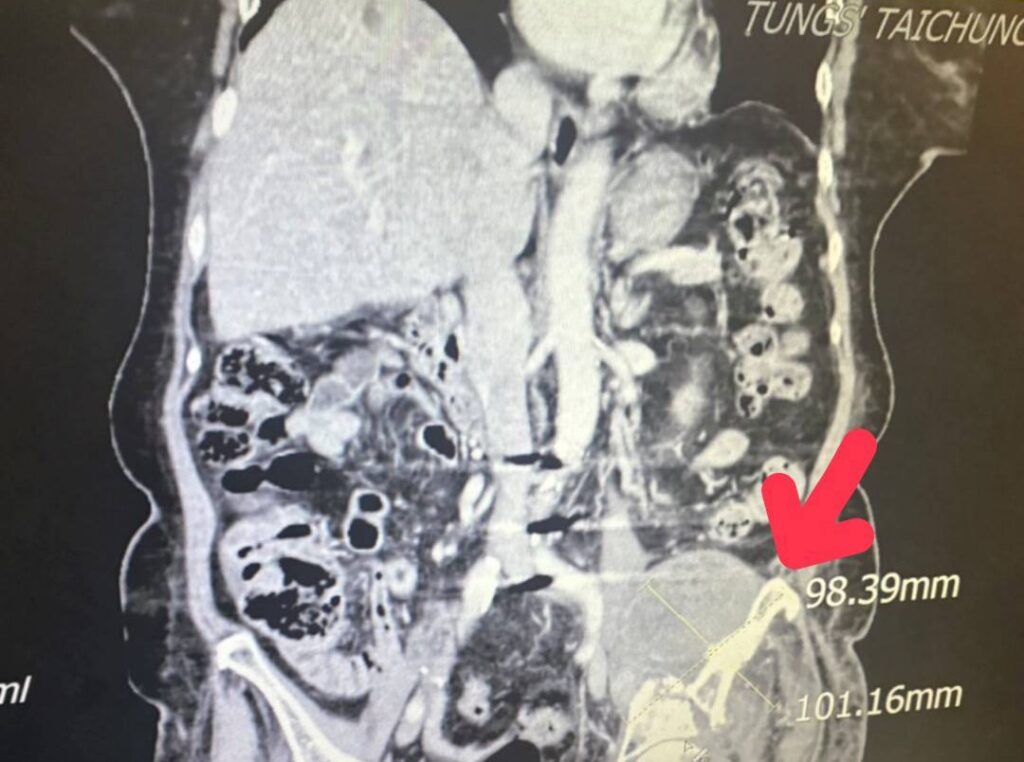

紅色箭頭即為進行銳視刀適應性放射治療利用空間分割點狀治療方式,配合傳統銳視刀治療方式,治療後腫瘤已經縮小至九點八公分x十點一公分。(記者孫義方攝)

但因腫瘤細胞太大(十二點一公分x十七點四公分),並且腫瘤位置執行手術風險過高,轉由放射腫瘤科葉啟源主任進行銳視刀適應性放射治療,利用空間分割點狀治療方式在局部的位置給予點狀高劑量的放射線,再配合傳統銳視刀治療方式,經過一個月二十六次治療後,腫瘤已經縮小至九點八公分x十點一公分許,縮小腫瘤後也讓疼痛獲得明顯改善。